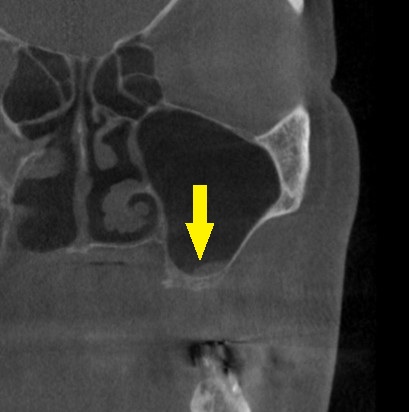

ご了承いただけましたので、本日、左側上顎のサイナスリフトを施行しました。

下の写真下段が手術後のCTです。